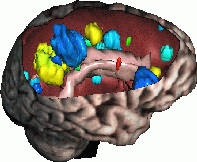

Atlas-based Brain Critical Structures Segmentation for Radiotherapy Planning

Brain radiotherapy must achieve two goals: the complete irradiation of the tumor, and the preservation of critical structures (brainstem, eyes, optical tracts, etc.). By customizing the shape of the irradiation beam and modulating the irradiation intensity, conformal radiotherapy allows to optimize the irradiation of the tumor and the critical structures. The planning of conformal radiotherapy requires accurate localizations of the tumor and the critical structures.

This work aims to delineate automatically the critical structures of the brain. In order to do this in a specific patient’s image, we use an anatomical atlas containing labels of the structures of the brain. This atlas is registered on the patient image by a global followed by a non rigid registration. The aim of this work is basically to develop a non rigid registration algorithm adapted to anatomical structures registration. The second goal is then to validate the method we propose using quantitative measures on manually delineated patients.

Contacts: Grégoire Malandain.

More details are here.